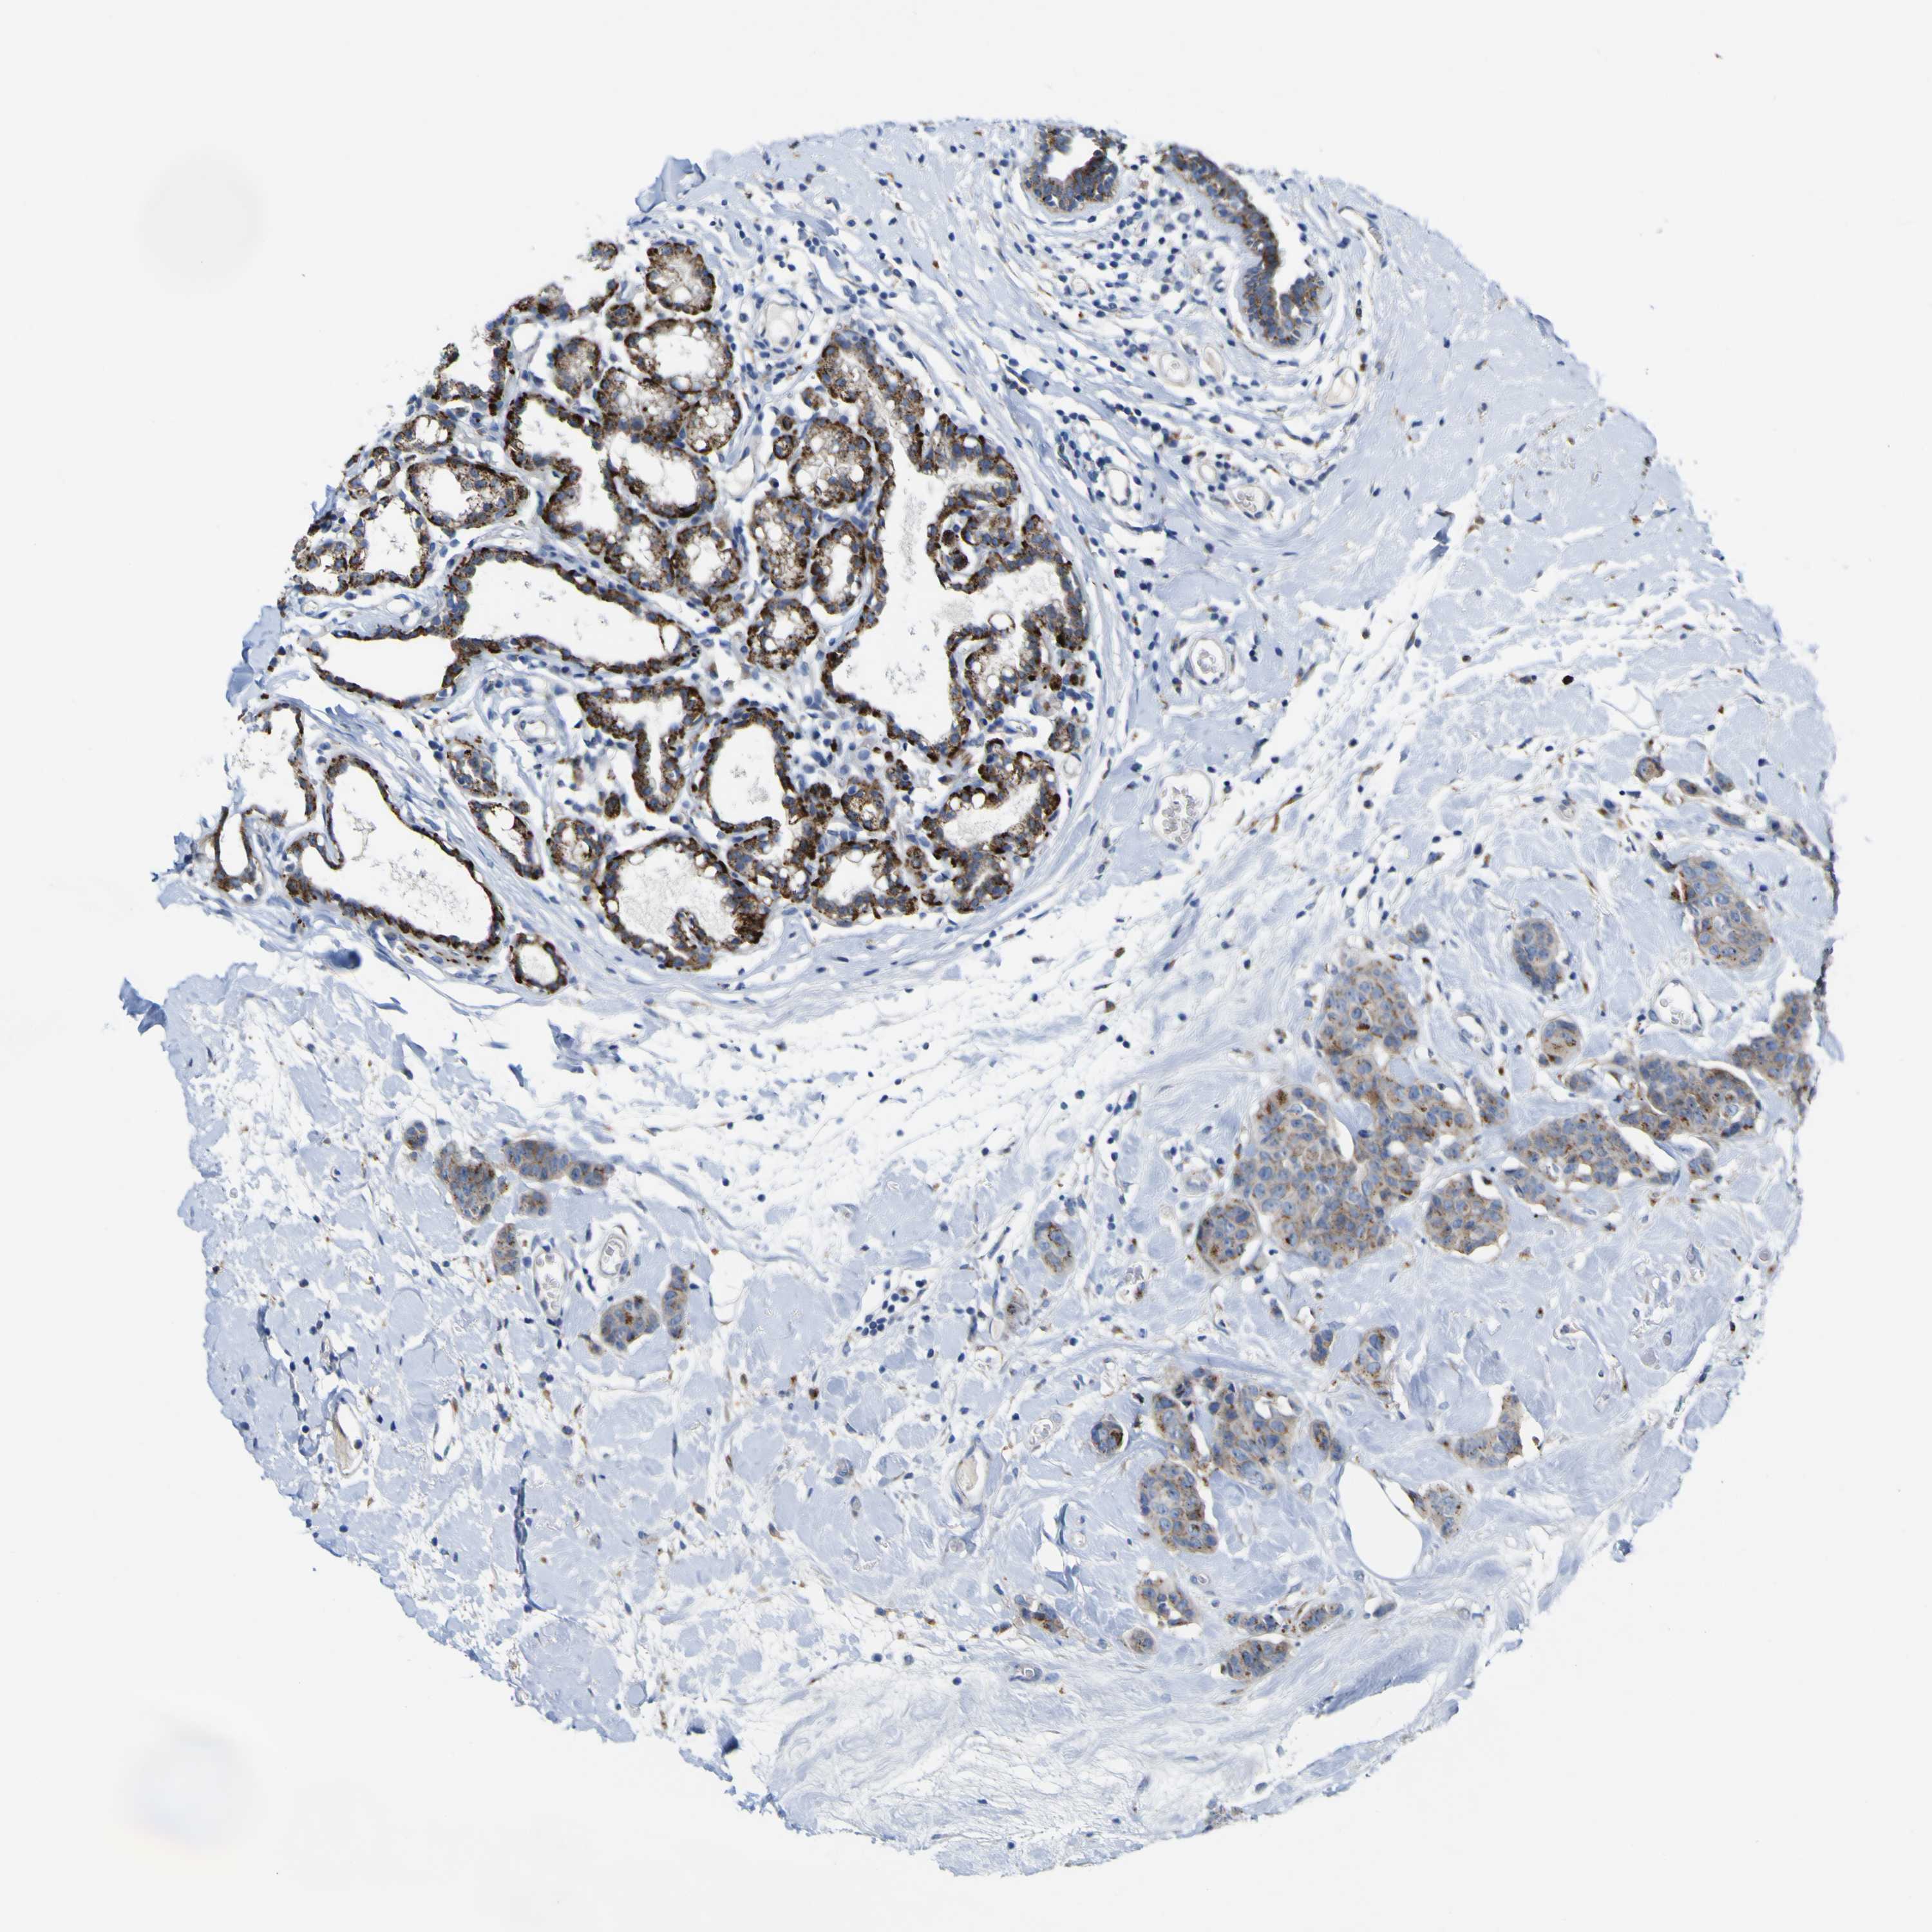

CANCER BREAST CANCER Show tissue menu

BRCA TCGA BRCA VALIDATION PROTEIN EXPRESSION